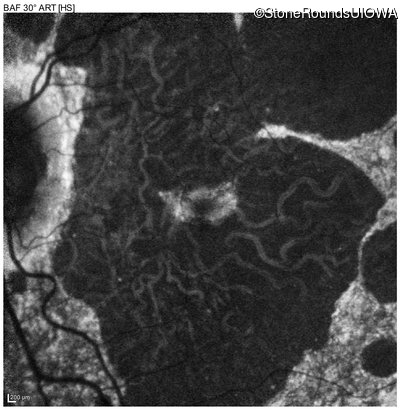

Blue Autofluorescence - Right - 20/40 -2

Exemplar

Blue Autofluorescence - Left - 20/40 +1